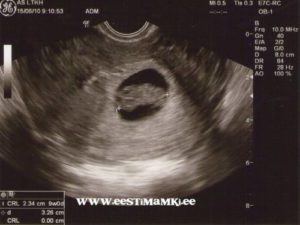

УЗИ

На протяжении беременности каждая женщина должна пройти три плановых УЗИ. Срок проведения плановых исследований:

- первое УЗИ назначается на срок от 10 до 12 недель;

- второе УЗИ проводят, когда срок беременности составит от 18 до 22 недель;

- третье УЗИ нужно будет пройти ближе к родам, когда срок составит от 33 до 35 недель.

Помимо плановых УЗИ могут быть назначены и дополнительные, если появятся показания.

Совет! Проведение УЗИ не оказывает отрицательного влияния на плод, поэтому будущие мамы не должны бояться, если врач рекомендует пройти дополнительное обследование.

Стоит ли делать УЗИ на 9 неделе? Ведь первое плановое обследование назначают не ранее 10 недели? Ответить на эти вопросы сможет только врач. Возможно, он перенесет УЗИ на неделю, когда срок беременности достигнет 10 недель. А может быть порекомендует не ждать 10 недели, а пройти обследование немедленно. Как правило, УЗИ ранее 10 недели назначают:

- при подозрении на внематочную беременность;

- для подтверждения или исключения многоплодной беременности;

- для выявления патологий плода, плаценты, матки;

- подозрение на то, что беременность перестала развиваться.

Если же особых показаний нет, то врач, как правило, рекомендует дождаться 10 недели и пройти плановое исследование. Но даже в том случае, если врач не советует ждать наступления 10 недели, будущая мать не должна пугаться.

Внеплановое исследование вполне может подтвердить, что с плод развивается нормально. То есть, оно нужно еще и для того, чтобы будущая мама перестала волноваться. Ведь нервозность матери отрицательно влияет на развитие плода.